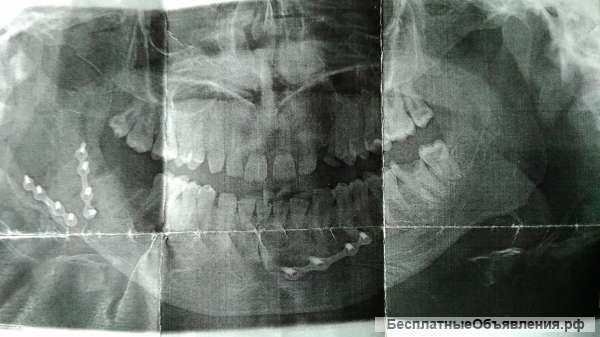

Приветствую всех! Я нуждаюсь в помощи деньгами, дело в том что у меня была операция на нижней челюсти, и после операции выявилось осложнение, челюсть заузилась, стал неправильный прикус, нарушена дикция. Требуется повторная операция которая стоит денегв размере 60000 руб. Прошу всех помощи, не раз обращался в разные соц.сети и везде отказ! Это не обман и не мошенничество, все так как описано и мне действительно очень нужны деньги. Помогите пожалуйста с моей проблемой .